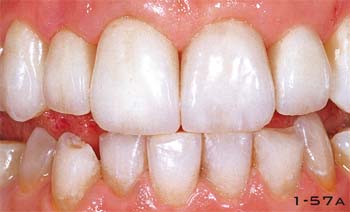

Abb. 1-57a Klinisches Bild: Frontzähne versorgt mit fluoreszierendem Keramikmaterial. Der Vergleich mit den Unterkieferzähnen zeigt eine exzellente ästhetische Integration.

Abb. 1-57b Nahaufnahme zehn Tage nach dem Einsetzen der definitiven Versorgung.

Abb. 1-57c und 1-57d Nahaufnahme des Lächelns vor und nach der Behandlung.